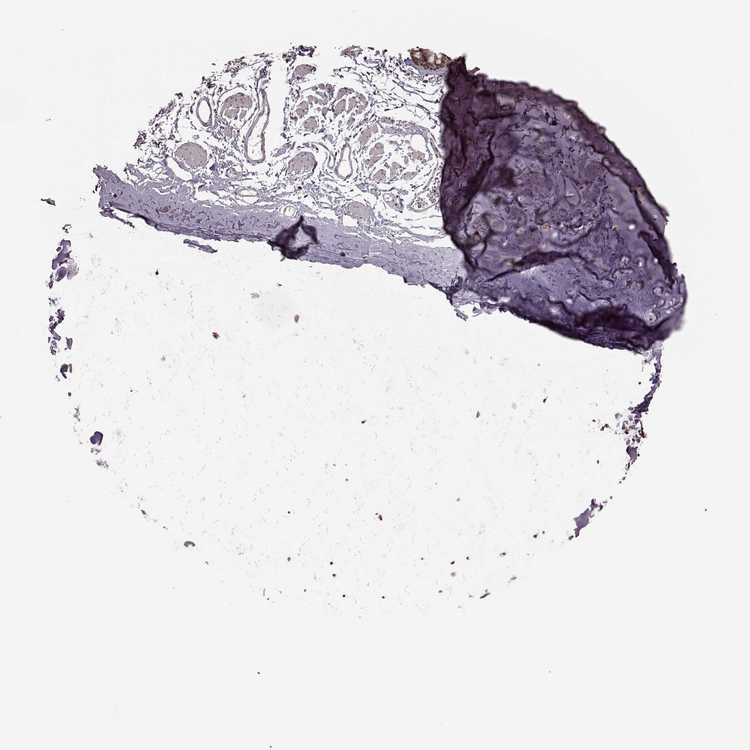

SOFT TISSUE 1 - Antibody stainingi

Antibody staining in the annotated cell types in the current human tissue is reported as not detected, low, medium, or high, based on conventional immunohistochemistry profiling in selected tissues. This score is based on the combination of the staining intensity and fraction of stained cells.

Each image is clickable and will lead to virtual microscopy that enables deeper exploration of all samples and also displays staining intensity scores, fraction scores and subcellular localization as well as patient and tissue information for each sample.

Antibody HPA054508Antibody HPA059315

Chondrocytes LowLow

Fibroblasts Not detectedNot detected

Peripheral nerve Not detectedNot detected